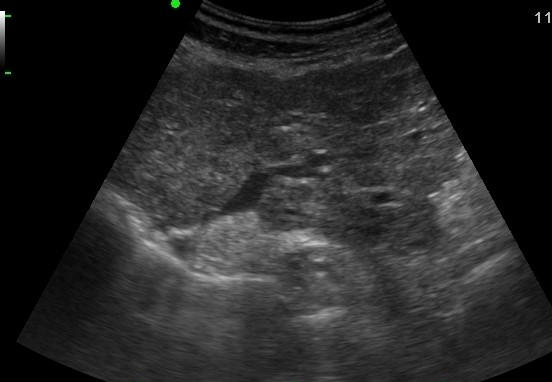

GB & BD ) лӢҙлӮӯ м„қнҡҢлҸҷл°ҳ 충мӢӨм„ұ л¶Ҳк· м§Ҳ лҸҷл“ұм—җмҪ” мў…кҙҙ |

2019.05.11 мЎ°нҡҢмҲҳ: 203 |